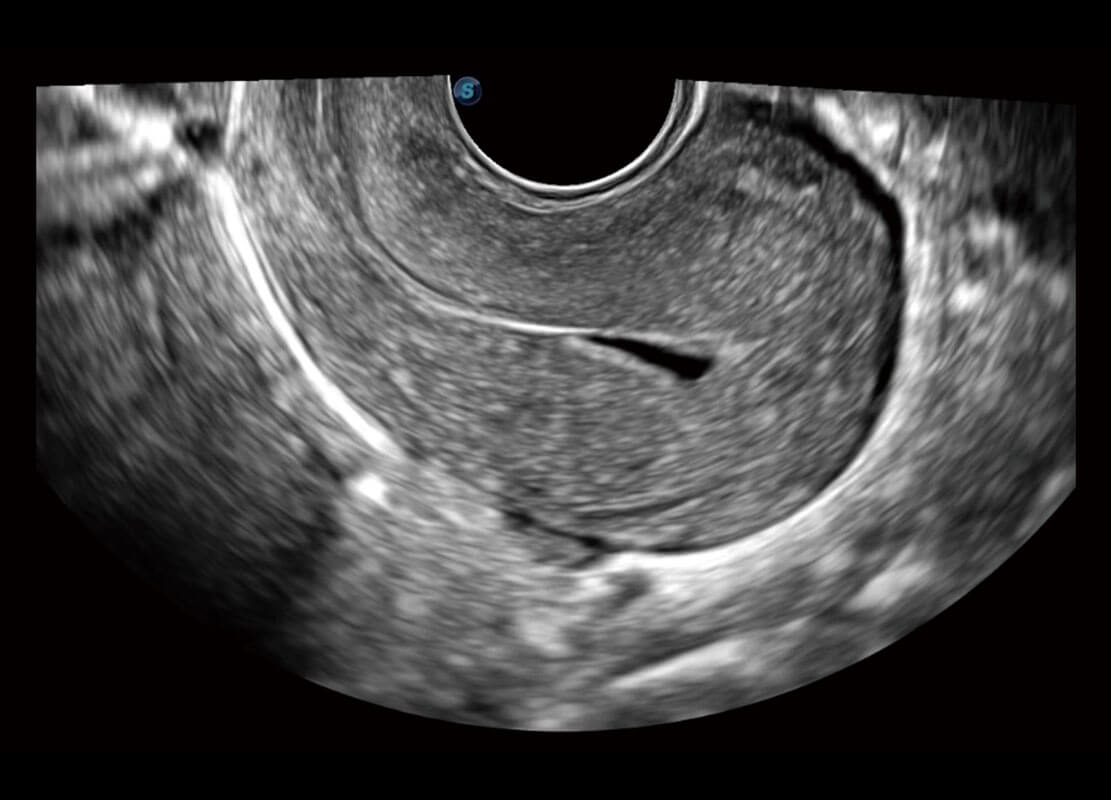

P60优异的图像质量搭载专科探头,在妇科基础疾病的诊断、卵泡生长的监测、输卵管通畅情况的判别等方面为您提供生殖应用方案。

腔内妇科-卵巢